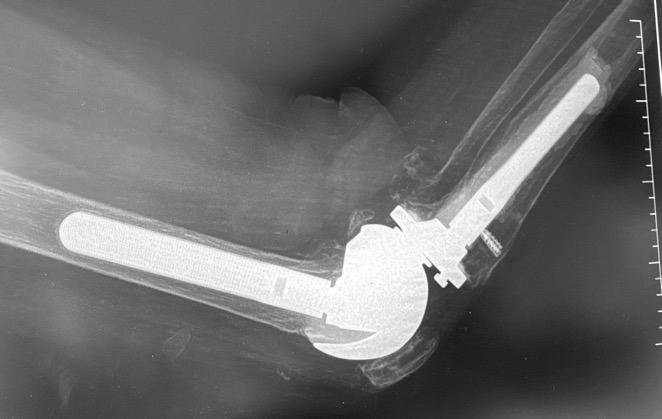

Case 2 is a 65-year-old woman with a previous oncological history and implantation with a TKA. Her knee became infected and required component removal and reimplantation with a rotating hinge. In 2013 she fell and tore patellar tendon and dislocated the patella. The patella was relocated, tear was repaired, and the protection technique used. (Figure 11A-B)

Her recovery was uneventful and was “doing great!” In 2015 (2-years following repair), she requested that the cable removed. Unfortunately, in 2016, she fell again and re-ruptured her patellar tendon. The rotating hinge was retained in place and the patellar repair / protection technique performed. She was recently seen in September of 2025 (9.5 years post second repair) and reports full independent activities of daily living (ADL) without ambulatory aids. She has a slight “lag” and weakness, so I requested that she use a cain when outside. She has ROM through 104 degrees, but that is due to the mechanical limits built into the rotating hinge device.